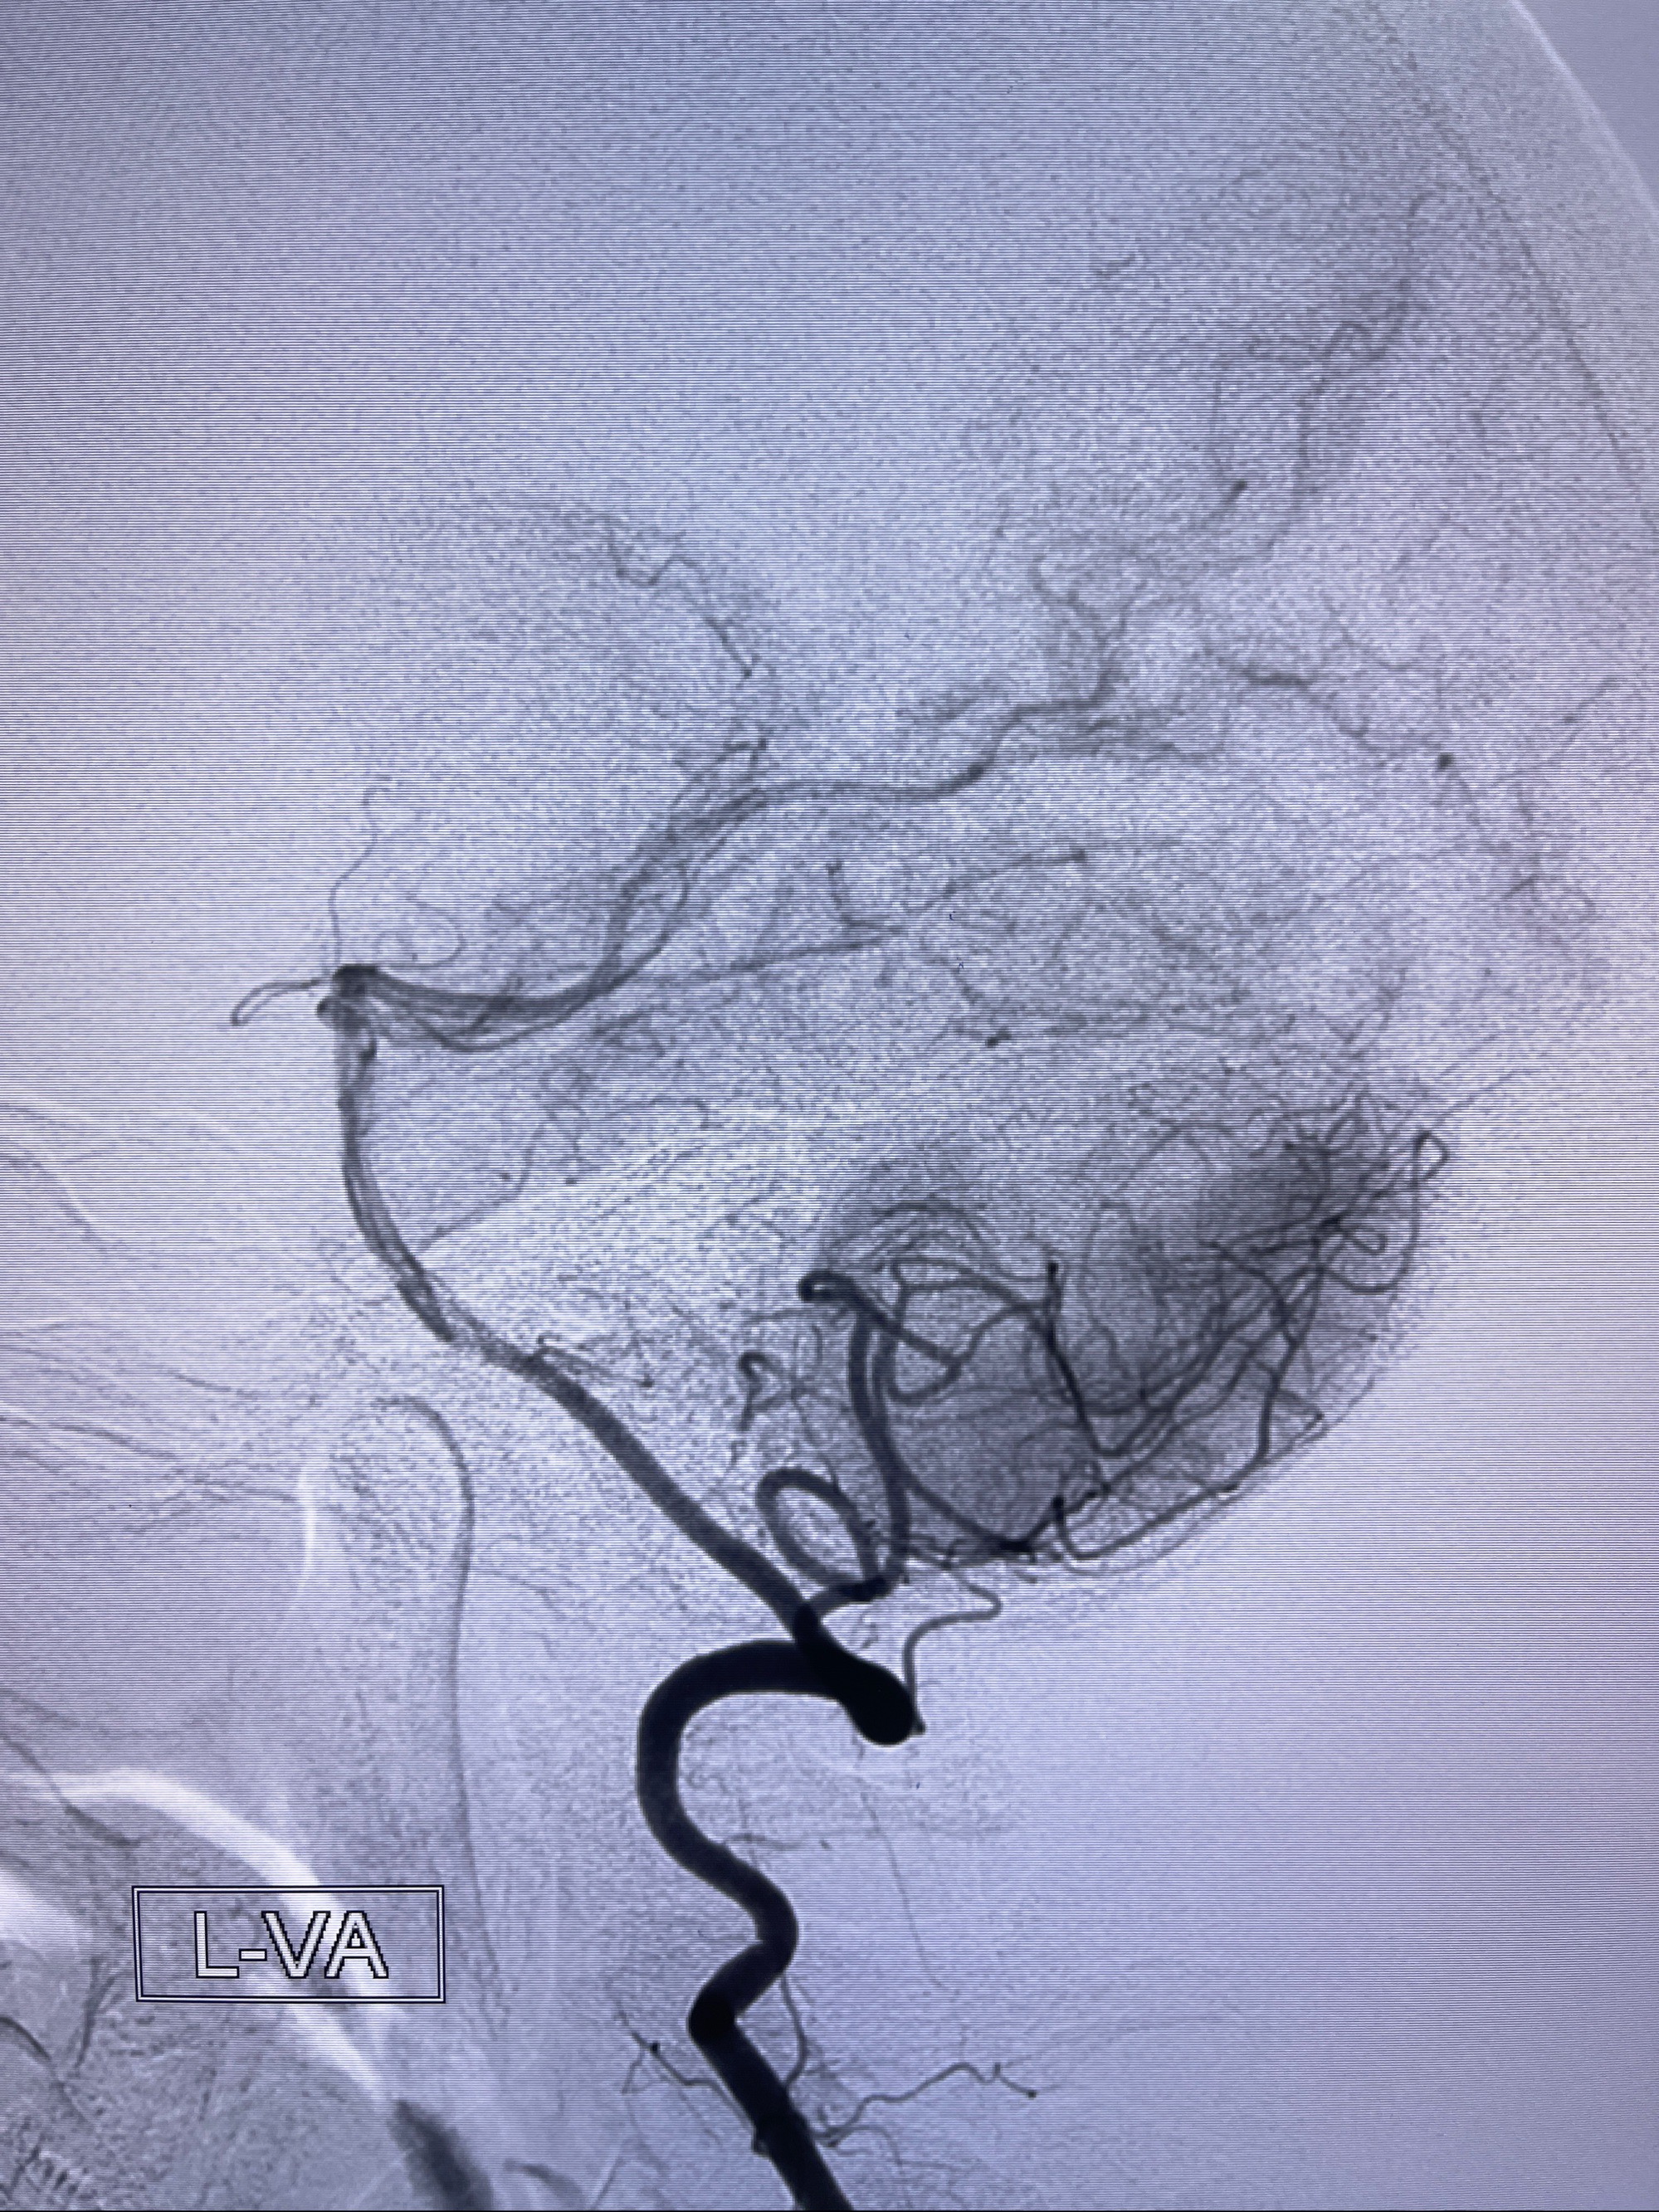

2023-08-14DSA:

左侧大脑中动脉动脉瘤,约2.6-2.8-3.4-2mm大小(瘤颈部、瘤体部、瘤高)

1.左侧大脑中动脉动脉瘤,约2.6-2.8-3.4-2mm大小(瘤颈部、瘤体部、瘤高)

2.外科手术夹闭or介入支架辅助栓塞